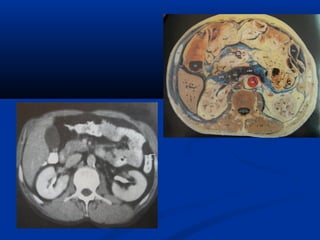

U maùu vuønghaømU maùu vuøng haøm (T)/(T)/ Daõn tónh maïchDaõn tónh maïch caûnh ngoaøi (T)caûnh ngoaøi (T)

Xaùc ñònh vò tríxöông söôøn treân CT